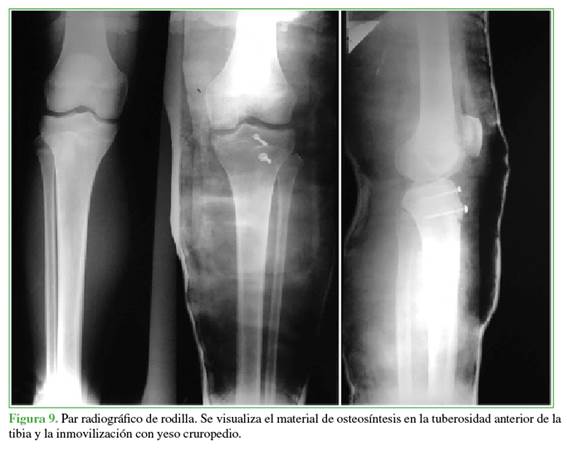

La cirugía consistió en una reducción abierta más osteosíntesis con colocación de dos tornillos paralelos sin afectar la fisis (uno en la región de la metáfisis y otro en la región de la epífisis). Durante la operación, se constató la lesión del tendón rotuliano con invaginación de las fibras distales en el foco fracturario, se continuó con su liberación y se realizó una sutura a nivel del periostio, en la región anterior de la tibia proximal (Figuras 4 y 5), se procedió a la reducción y osteosíntesis con dos tornillos paralelos de 3,5 mm y la colocación de arandela, ubicados en la epífisis y la metáfisis (Figuras 6-8). Se le colocó un yeso cruropedio en extensión sin carga por seis semanas para luego continuar con el tratamiento de rehabilitación (Figura 9).

Tres meses después de la cirugía, el paciente realizaba carga completa durante la marcha y la carrera, las radiografías no mostraron cambios ni se observaron complicaciones, el arco de movilidad era de 0º a 120º de flexo-extensión. A los seis meses de la operación, reanudó su práctica deportiva con una flexo-extensión de 0° a 135°, lo que mostró un buen arco de movilidad, sin dolor ni molestias.